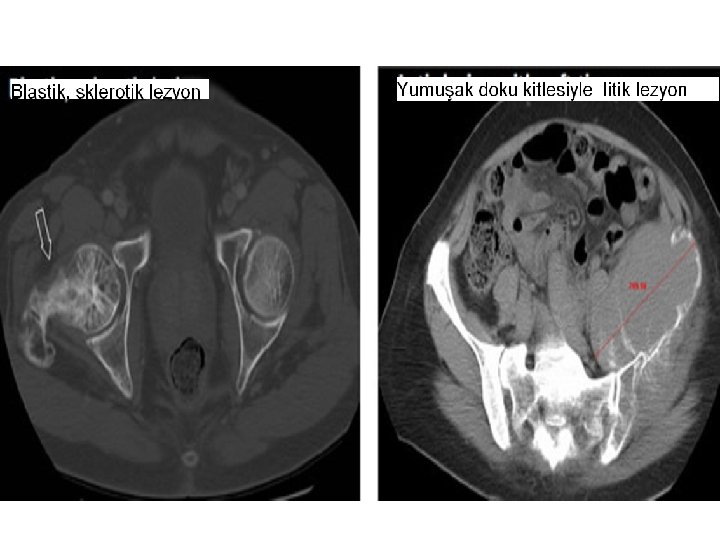

Kistik-Kemik Lezyonları • Basit kistler ölçülebilir ya da ölçülemeyen lezyonlara dahil edilmemeli. • Kistik metastaz mevcutsa ölçülebilir lezyon kriterlerine göre değerlendirilmeli. • Kemik lezyonlarını ölçmek için görüntüleme teknikleri yetersiz, varlığı ya da yokluğu değerlendirmeye alınmalı